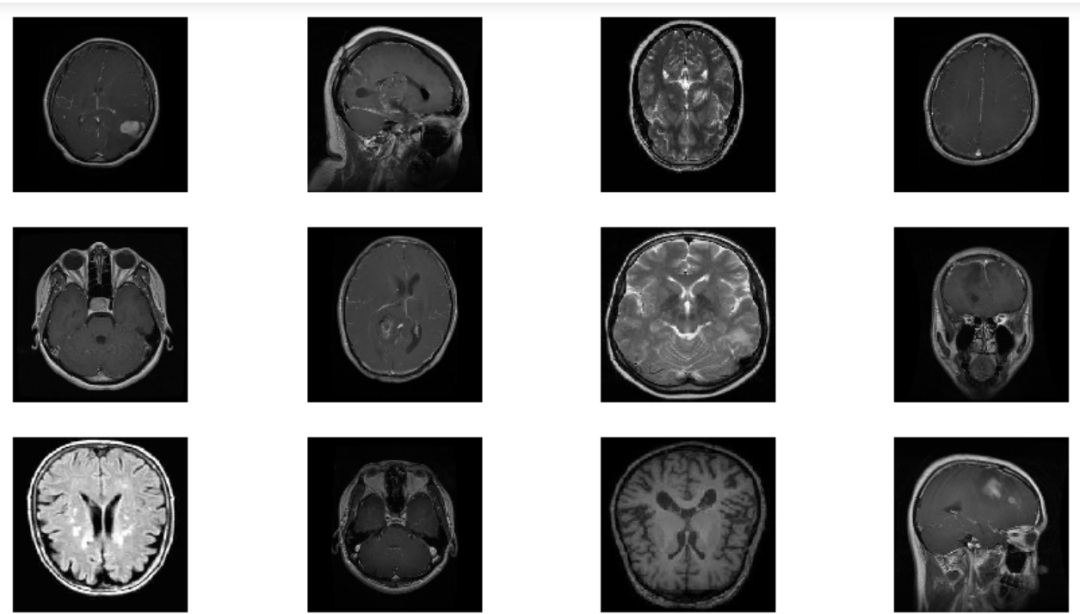

目前我们正在采用一个基于脑肿瘤图像的分类器数据集。该数据集中包含了 7022 张来自人的大脑MRI图像,并被划分为训练集和测试集两部分。这些图像被划分为4个类别。

胶质瘤(Glioma)

脑膜瘤 (Meningioma )

无肿瘤 (No tumor)

垂体(Pituitary)

这些图像的像素大小为 512 x 512,并且每个图像都有固定的标签。

现在让我们通过可视化我们的图像来观察图像增强是如何工作的,并通过使用我们的分类器来识别我们正在寻找的脑肿瘤类型。

它会给我们这样的输出,